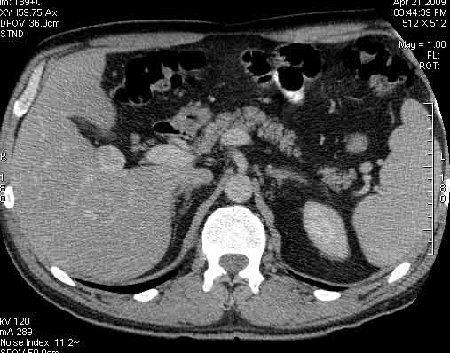

Сонограммы, КТ- артериальная, портальная и отсроченная паренхиматозная фазы

Сделали КТ (весьма похвальная тактика); по КТ: в артериальную фазу: периферическое усиление в виде сливающихся островков контраста, с центрипетальной направленностью. Венозная и отсроченная фаза-хорошее накопление контраста; образование практически изоденсно по отношению к паренхиме печени. Классика гемангиомы. Вуаля-диагноз на "тарелочке".